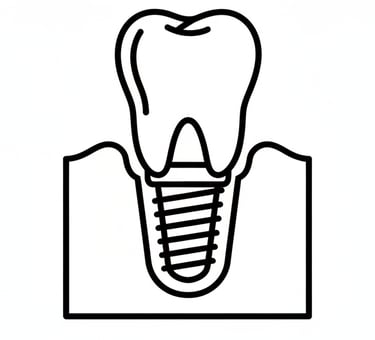

Οδοντικά εμφυτεύματα

Το οδοντικό εμφύτευμα είναι μια μικρή βίδα (συνήθως από τιτάνιο ή ζιρκόνιο) που τοποθετείται στο οστό της γνάθου στη θέση ενός χαμένου δοντιού. Λειτουργεί σαν τεχνητή ρίζα.